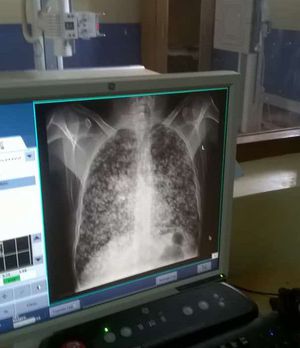

Radiograph

Chondroblastic osteosarcoma

Pulmonary oedema?

Mercury inhalation Miliary tb

Miliary tuberculosis , occupational lung disease

TBC or lung met